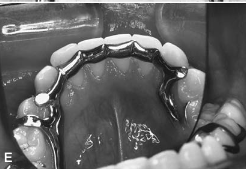

lingual bar major connector [illustration]

metal lingual bar major connector [illustration]

linguoplate major connector [illustration]